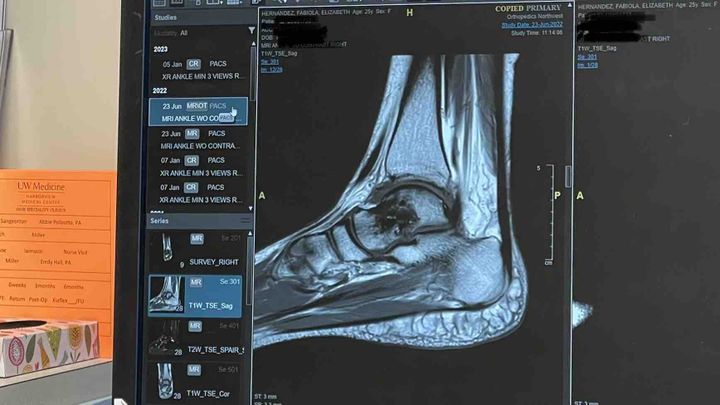

Long story short: I injured myself back on 5-11-21 and the hospital initially thought it was a tiny fracture. I had to wait a week to be seen by the only ankle orthopedic doctor in town, it was determined I sprained my ankle. I was told to be in a boot for a few weeks and to begin with physical therapy. If this wasn’t in the middle of Covid I wouldn’t have hesitated to go to Seattle for a second opinion/treatment but I decided to stay put and go with the dr here at home in Yakima. After a few weeks of PT, I returned to the Dr and kept pressing that something was not right, that it wasn’t just an ankle sprain. Finally an MRI was ordered and once results were read (3 months after injury) I still had a partially torn ligament and small bone bruise. One month later, I had surgery on 9-23-21. The surgeon came out and told my support person in the lobby “it was worse than I was expecting” and it’s only gotten worse since then. My small bone bruise has developed into Avascular Necrosis (lack of blood flow to the bone) resulting in arthritis. After seeing three different doctors in the Seattle area, being instructed to rest as much as possible, being on crutches and a knee scooter, being prescribed a bone stimulator (not covered by insurance) and now being given what feels like a real option— a hybrid prosthetic called an Exosym. I was finally able to walk without pain for the first time in nearly two years. I couldn’t believe it… But this is why I’m reaching out to you, I need your help to access this device. I was quoted $4081.86 for the Exosym and I need to have half of that down by my appointment next week or I have to further push back accessing this relief. If you’re able to give any amount, it would be greatly appreciated. And if you’re a person of faith, please say a prayer for me that this is the medical intervention that restores my body and that I’m able to meet this need. I thank you all for your love and support as I begin to open up about my journey to healing.

I severely sprained my ankle back on May 11, 2021 when I was out with my pup and a friend. I was being a good dog owner and “cleaning up” after my puppy. Rather than walking my dog around the retaining wall I figured I could quickly climb over the wall to get to the trash. A 30 second shortcut has cost me so much… I had so much regret, I have told myself a million times “I should have just walked around that wall” with the help of my amazing therapist I’ve come to accept that had I “walked around that wall” I still may have hurt myself and I would have told myself “I should have climbed over that wall”. Due to Covid I decided it would be best and the most responsible thing to stay in Yakima for treatment rather than seek out medical care in the Seattle area. And I also I wanted to have faith that Yakima didn’t have the poor medical care everyone always talks negatively about but the horrible reality of medical system being for profit & being in a rural-like community there is only one ankle orthopedic doctor. I was brushed over, I wasn’t listened to when I expressed something was wrong, I was made to feel I didn’t know what I was talking about when listening to my body and that “it wasn’t that bad”. After repeat visits, many physical therapy appointments (2x a week for 4 weeks) and months passing from the initial injury, Dr’s PA requested an MRI in July, the MRI was done in early August and appointment to go over the results wasn’t until late August. The MRI revealed I had a partially torn ligament explaining the reason for prolonged ankle instability, they also found a SMALL bone bruise. Surgery was scheduled for 9-23-21 to repair the ligament.

Surgery day comes and I’m hopeful this will be the real beginning to healing in addition the the 6 weeks of physical therapy I was going to have to go through after once approved. I planned for this the best I could, I budgeted to the best of my ability for surgery and 6 weeks of PT. When the physician came out of my surgery, he found my support person in the waiting room to update them and he himself said “it was worse than I was expecting.” That is not what you want to hear AFTER this person just operated on you. After a year of me continuing to say something is not right, we finally did an updated MRI in Yakima, the results were bad, very bad. It was discovered that my small bone bruise had worsened after surgery, I had lost blood flow to the bone and developed Avascular Necrosis. I now have arthritis in the Talus bone. I’ve been asked if I’m an alcoholic, cancer survivor, steroid user and none of those apply to me; further indicating arthritis of that one specific bone was likely caused by my injury or my care. I now have the ankle of a 60 year person. After my original surgeon went over the MRI results months after surgery (May 2022) he told me to go get a second opinion and when I asked “okay, I will. But what are WE going to do next?” He responded with “we’ll talk about it at a later date but for now go get a second opinion” that was the last time I spoke to him as called once a week for four weeks straight and never got a call back from his assistants or the clinic. My original surgeon, for a lack of a better term, ghosted me.